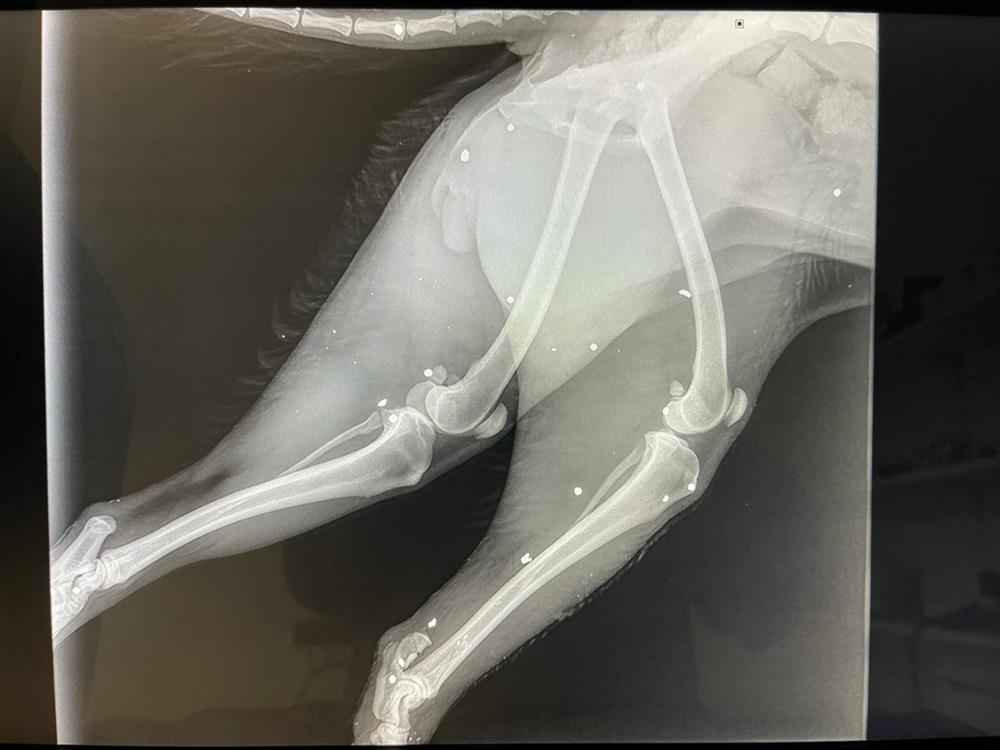

Ένα αποτρόπαιο περιστατικό κακοποίησης ζώου σημειώθηκε στο Αρκαλοχώρι του Δήμου Μινώα Πεδιάδας, στο Ηράκλειο, προκαλώντας σοκ και αγανάκτηση. Σύμφωνα με πληροφορίες, άγνωστος δράστης φέρεται να επιτέθηκε σε ένα μικρόσωμο σκυλάκι, προκαλώντας του σοβαρά τραύματα στα άκρα. Σαν να μην έφτανε αυτό, στη συνέχεια το πυροβόλησε, ολοκληρώνοντας την αποτρόπαια πράξη του.

Οι κτηνίατροι δεν κατάφεραν να σώσουν το ένα πόδι της σκυλίτσας, με αποτέλεσμα να προχωρήσουν σε ακρωτηριασμό, ενώ της τοποθέτησαν και νάρθηκα. Περαστικοί το βρήκαν στην άκρη του δρόμου να ουρλιάζει από τους φρικτούς πόνους.